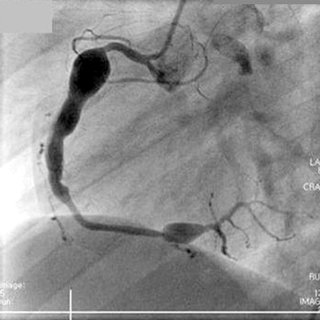

심장 및 혈관계의 관상동맥류가 가장 심각한 합병증입니다.

관상동맥은 심장을 먹여 살리는 혈관으로, 여기에 혈관꽈리, 혈관류가 발생합니다.

거대 관상동맥류로 직경이 8mm 이상크기가 발생하여, 파열되거나,

혈전형성에 의해서 심근경색의 위험이 발생합니다.

이러한 관상동맥류는 가와사키가 제대로 치료되지 않는 경우 20%에서 발생하여,